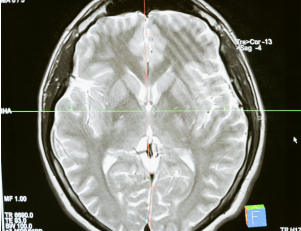

Imagerie médicale : les dessous numériques d'une histoire physique

Conférence de Nicolas Passat (professeur au CRESTIC), mars 2025